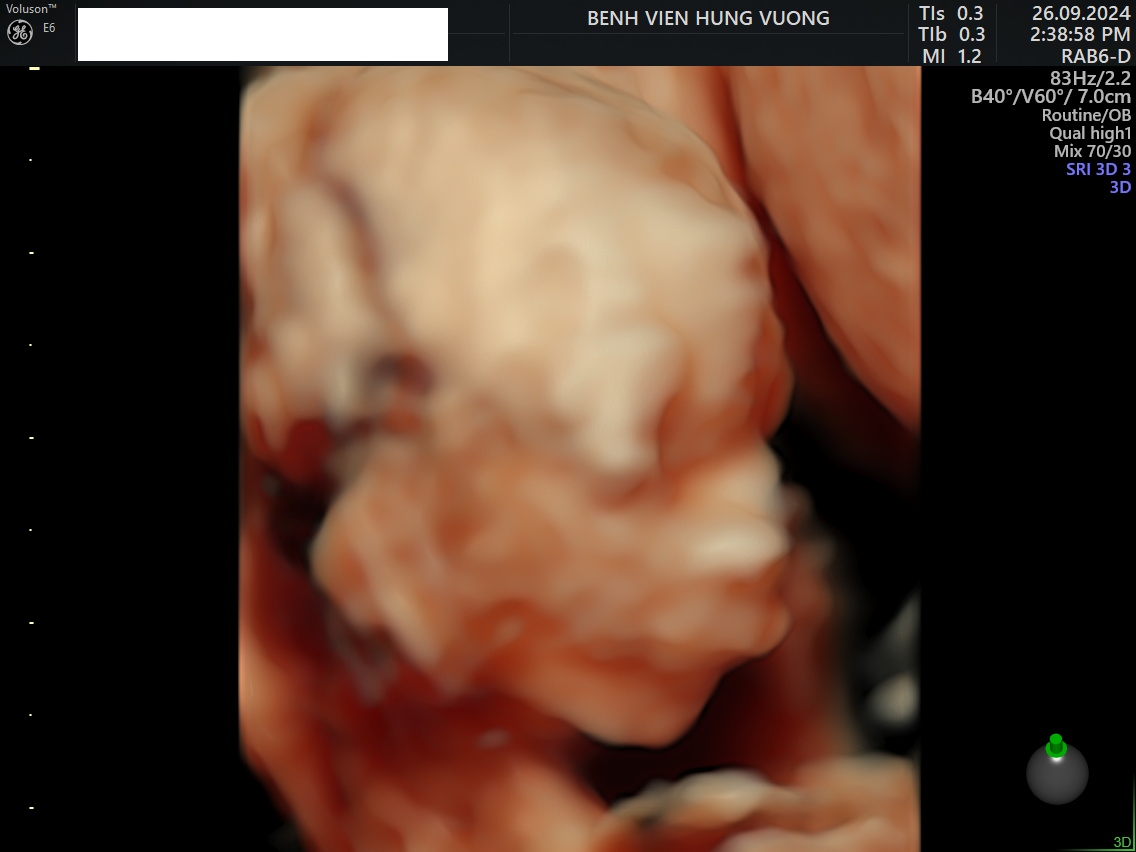

Hội chứng Pierre Robin

Hội chứng Pierre Robin (Pierre Robin Syndrome - PRS), còn gọi là chuỗi Pierre Robin, là một dị tật bẩm sinh hiếm gặp xảy ra trong quá trình phát triển thai nhi. Đây là một nhóm các tình trạng ảnh hưởng đến cấu trúc hàm và miệng của trẻ, dẫn đến khó khăn trong việc thở, bú mẹ hoặc ăn bằng bình sữa. Hầu hết trẻ em mắc hội chứng này sẽ được chẩn đoán ngay sau khi sinh.

- Hàm dưới và cằm nhỏ (micrognathia): Hàm dưới nhỏ hoặc lùi về phía sau.

- Tụt lưỡi về phía sau họng (glossoptosis): Lưỡi có xu hướng rơi xuống phía sau, gây tắc nghẽn đường thở.